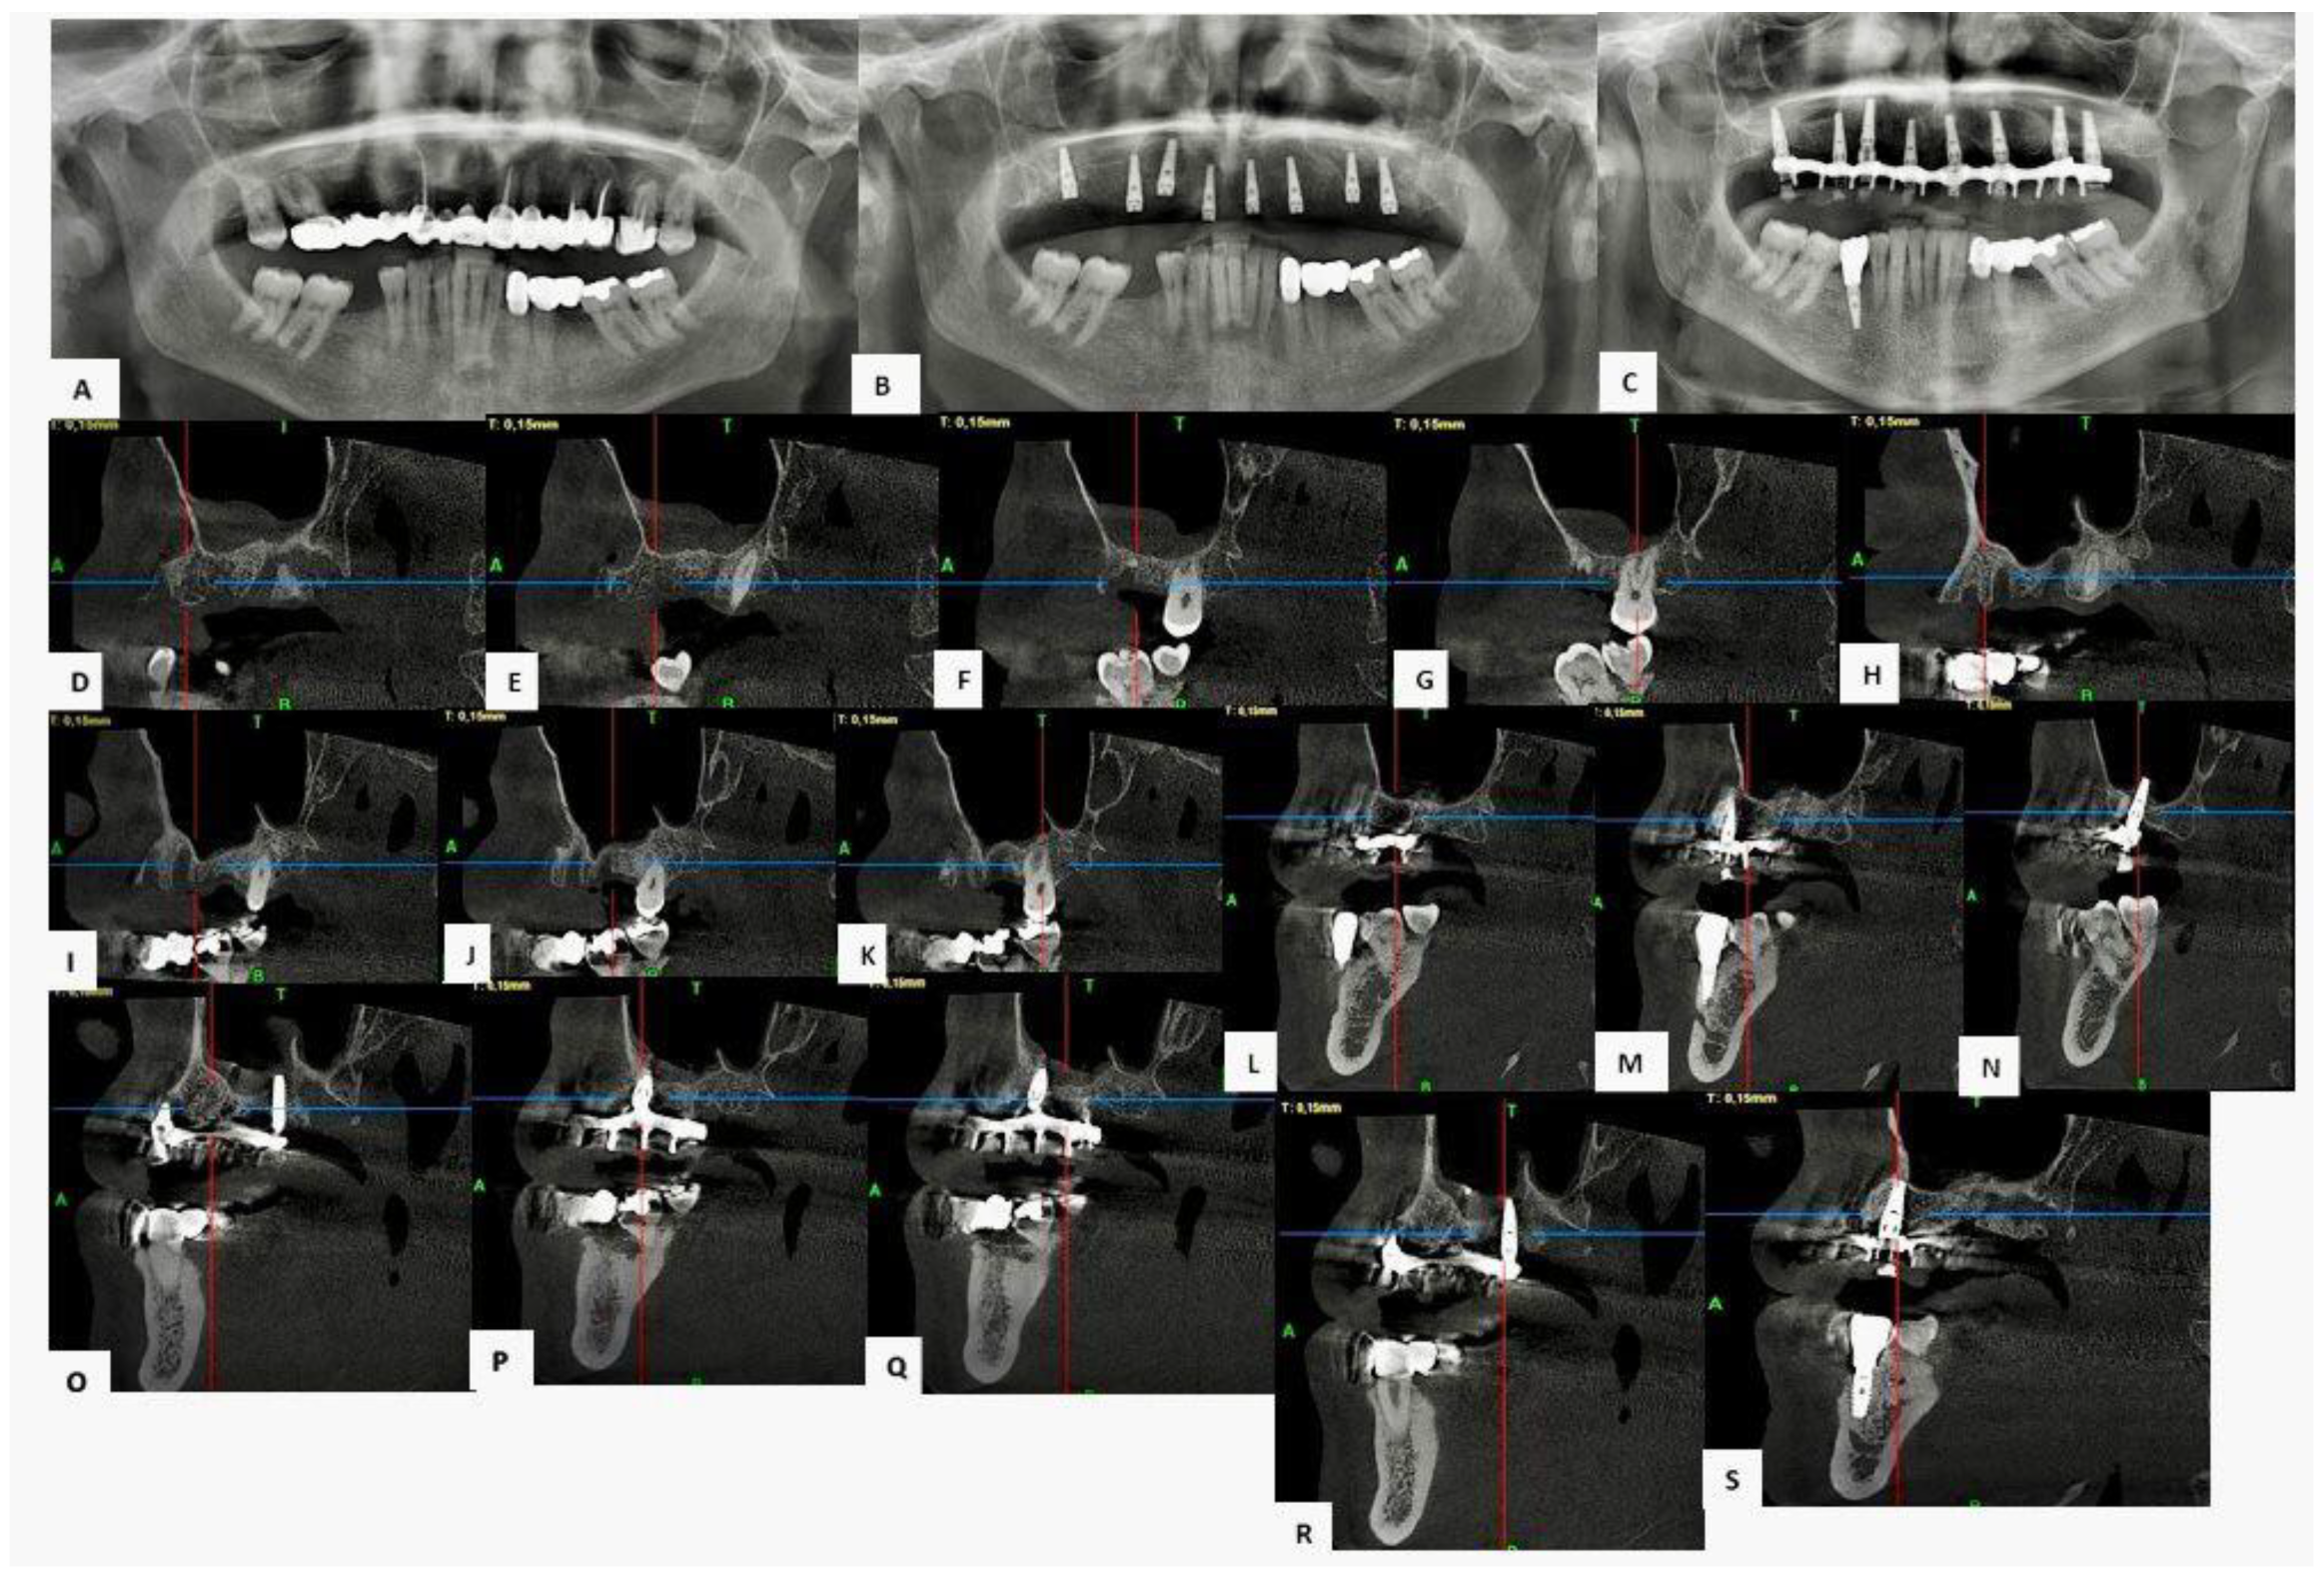

3.3.1. Case 1—Female Patient, 52 Years Old

3.3.2. Case 2—Female Patient, 60 Years Old

3.3.3. Case 3—Male Patient, 58 Years Old

4.2. Considerations on Representative Clinical Cases